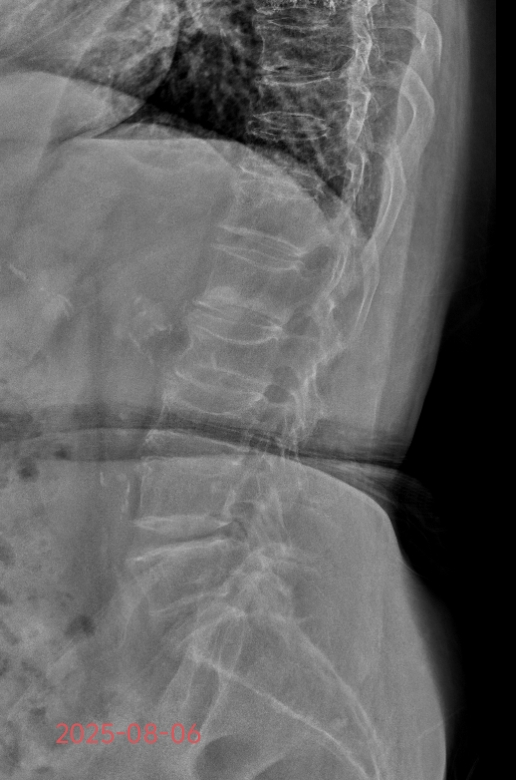

“突发腰部剧痛,无法翻身及坐起活动”。今年82岁的方奶奶,既往有糖尿病、高血压、心脏病,长期口服药物治疗,曾有口服糖皮质激素药物病史。2025年8月5日出现夜间腰部剧痛,急诊来院就诊,急查腰椎核磁诊断为腰椎骨质疏松伴腰1椎体骨折。随着年龄增长,老年群体骨骼密度下降,椎体如同“脆弱的蛋壳”,日常弯腰、咳嗽都可能引发骨折,剧烈疼痛与活动受限让不少老人陷入“卧床难起”的困境。

方奶奶入院后,骨科团队全面评估其心肺功能等指标,量身定制PKP手术方案。主治医师王亮在局部麻醉下通过微小切口,在影像精准引导下将穿刺针植入病变椎体,注入骨水泥加固,水泥弥散良好。整个过程耗时不到1小时,创伤小、出血少,术后无需长时间禁食。